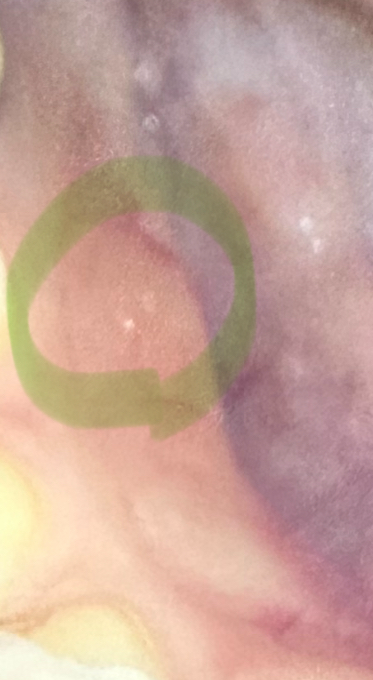

과자먹은 후 이질감이 느껴져서 보니 침샘 안 벽면에 오돌토톨 하얀색이 났어요

사진처럼 하얀색 알갱이 같은 오돌토돌이 한두개

생겼어요 ㅠ ㅠ 통증 없습니다

하얀알갱이 같은것과 수포 ? 같은 느낌입니다

• 1번 째 사진